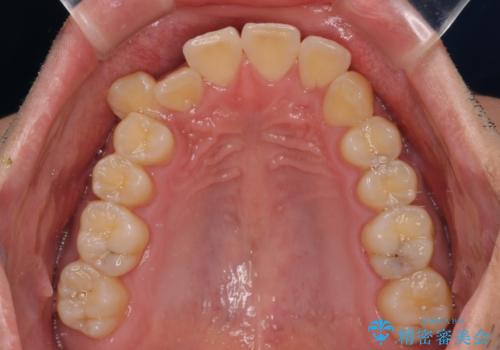

- 前歯のデコボコと右上の八重歯を気にして来院された患者様です。

マウスピース矯正とワイヤー矯正で悩んでいらっしゃいましたが、非常に強い咬合力であることや、お仕事柄不規則な生活リズムになることが多いとのことで、ワイヤー装置にて矯正治療を行うこととしました。

口元が突出する仕上がりとならないように、舌突出癖改善のトレーニングをしっかりと行っていただきながら、矯正治療を進めていくこととしました。